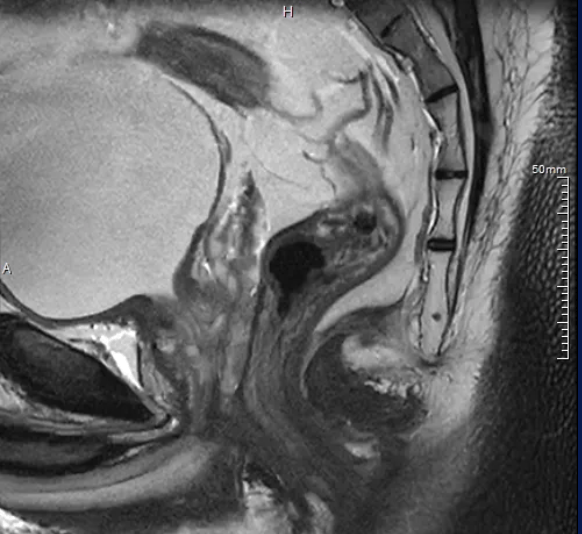

12月,高尚健康集团上海中心与上海长征医院携手,以“基于PET/MR一体化影像数据及AI后处理的盆腔解剖学三维重建手术规划的临床实践与应用”为研究方向,通过对上百例患者开展结直肠专项筛查,完成了相应的科研论证工作。